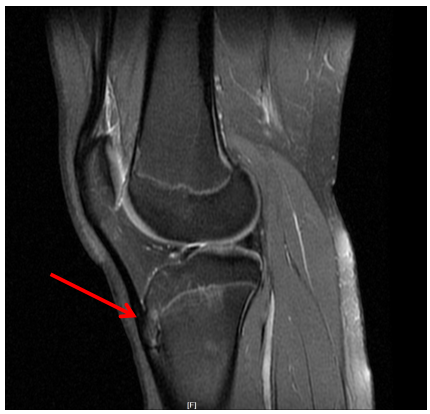

磁共振检查(MRI)是一项诊断胫骨结节骨骺炎的高敏感性、无辐射检查。主要表现为胫骨结节处骨骺增大,信号不均匀伴骨髓水肿;胫骨结节前上缘可见游离骨片影;髌腱下段胫骨结节附着处增粗,T2抑脂序列信号增高;局部软组织肿胀、水肿等影像特点。